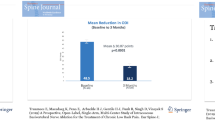

At a minimum of 5 years following BVN ablation, patients reported a significant mean reduction in ODI of 25.95 ± 18.54 (60.6%) compared to a baseline of 42.81 (p < 0.001). See Fig. 2.

Mean reduction in VAS at 5-year post-BVN ablation was significant at 4.38 ± 2.35 points on a 10-point scale from a baseline of 6.74 (p < 0.001). Sixty-six percent (66%) of patients reported a > 50% reduction in VAS, 47% reported a > 75% reduction in VAS, and 34% of patients reported complete pain resolution. See Fig. 3.